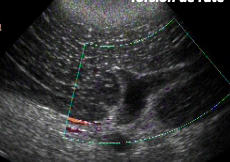

Expliquez le mode Doppler. Qu’est-ce qu’indique la couleur bleu et la couleur rouge?

A

=> des particules en mouvement génèrent des échos de fréquence différente de celle des US incidents

=> permet l’évaluation du flot sanguin

=> le chg de fréquence dépend de la direction et de la vitesse des particules : échelle de couleur concomitante

sur l’image :

• bleu : veines drainent loin de la rate

• rouge : artères vers la rate